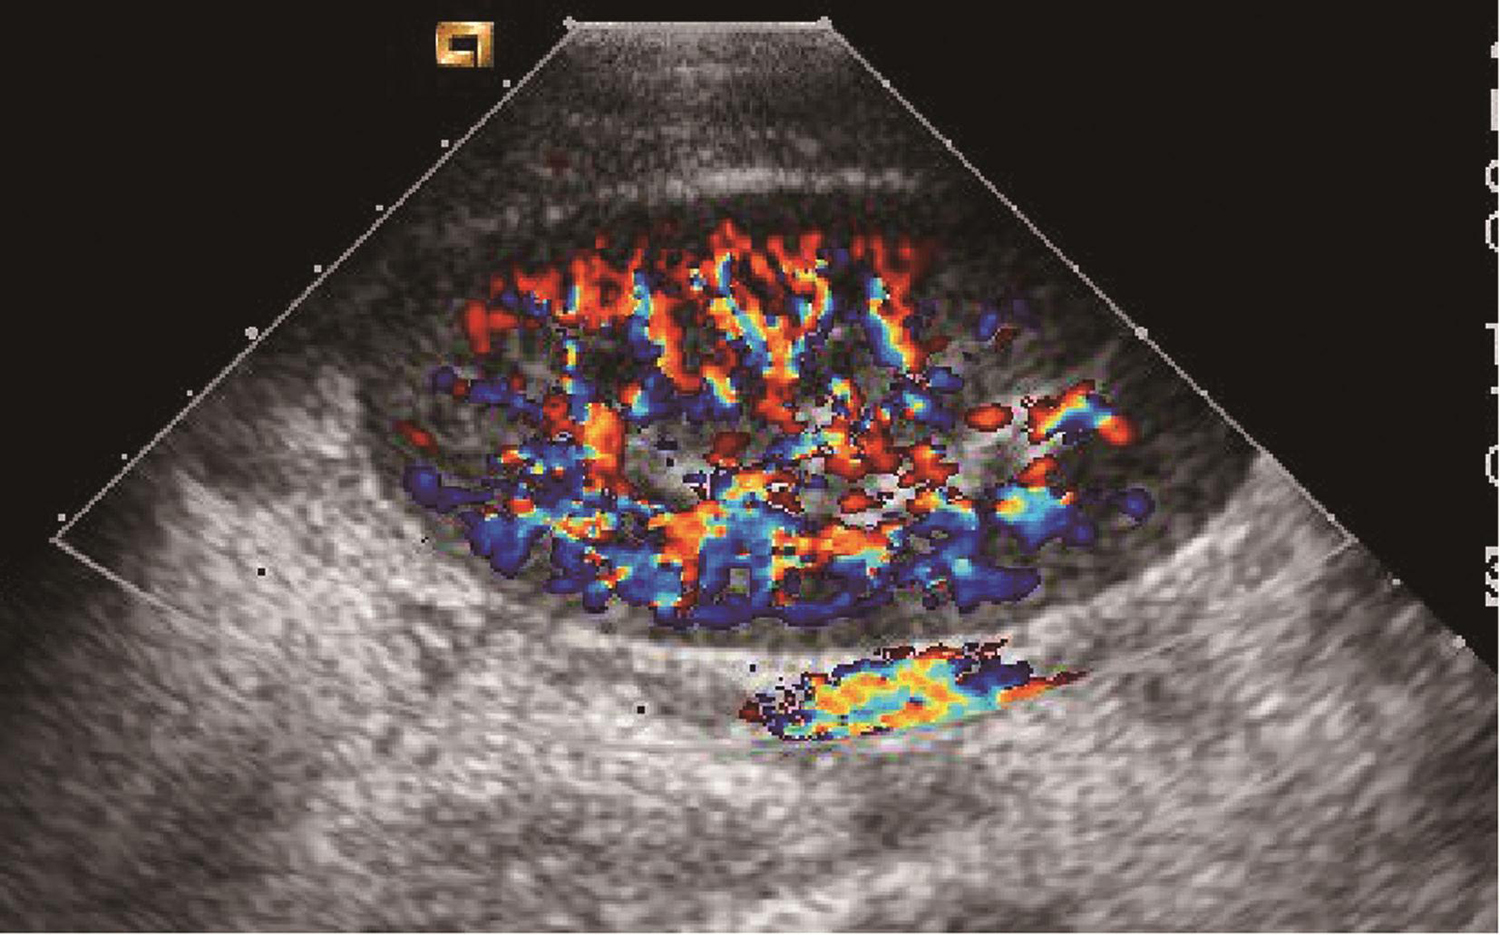

(3)彩色多普勒成像(color Doppler flow imaging,CDFI):

采用多声束进行快速采样,对所获得的多普勒频移(速度)信息进行自相关处理和彩色编码。将朝向探头的血流标记为红色,背向探头的血流标记为蓝色,以彩色亮度显示速度的高低,并将其叠加于二维声像图上的相应位置,获得血管在组织内的空间分布和实时血流速度信息(图1-1-3-6)。

图1-1-3-6 彩色多普勒成像显示肾脏的血流